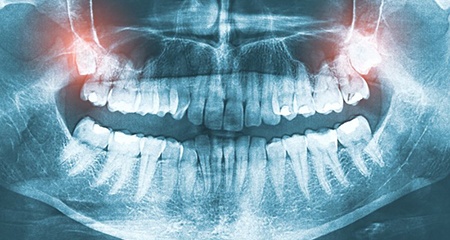

Wisdom teeth are the four molars at the very back of your mouth – though not everyone has all four. Since they’re the third set of molars that come in, they’re also known as “third molars.” Wisdom teeth typically emerge during teenage years or young adulthood. Either way, they should be the last set of teeth to fully develop.

Technically, not all wisdom teeth need to be removed. Some people are able to grow them in without complication. The problem occurs when the molars become “impacted” – meaning they become fully or partially trapped below the gumline. Impacted wisdom teeth can cause serious oral health issues if left untreated, including:

Many know it’s time to remove their wisdom teeth when they experience pain, but it’s worth noting that just because you don’t feel any discomfort doesn’t mean your third molars are safe to keep. The only way to know for sure is to visit your dentist in Gainesville for an exam.